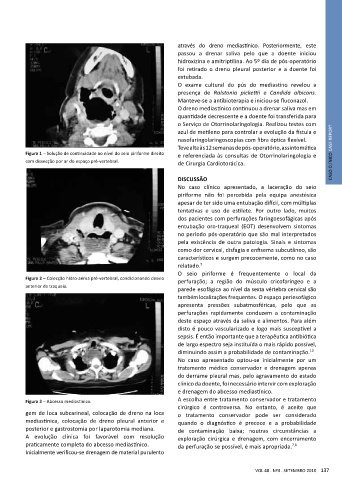

O seio piriforme é frequentemente o local da

Figura 2 – Colecção hidro-aérea pré-vertebral, condicionando desvio perfuração; a região do músculo cricofaríngeo e a

anterior da traqueia.

parede esofágica ao nível da sexta vértebra cervical são